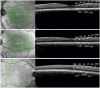

Oculocutaneous albinism (OCA) and ocular albinism (OA) are inherited disorders of melanin biosynthesis, resulting in loss of pigment and severe visual deficits. OCA encompasses a range of subtypes with overlapping, often hypomorphic phenotypes. OCA1 is the most common cause of albinism in European populations and is inherited through autosomal recessive mutations in the Tyrosinase (TYR) gene. However, there is a high level of reported missing heritability, where only a single heterozygous mutation is found in TYR. This is also the case for other OCA subtypes including OCA2 caused by mutations in the OCA2 gene. Here we have interrogated the genetic cause of albinism in a well phenotyped, hypomorphic albinism population by sequencing a broad gene panel and performing segregation studies on phenotyped family members. Of eighteen probands we can confidently diagnose three with OA and OCA2, and one with a PAX6 mutation. Of six probands with only a single heterozygous mutation in TYR, all were found to have the two common variants S192Y and R402Q. Our results suggest that a combination of R402Q and S192Y with a deleterious mutation in a 'tri-allelic genotype' can account for missing heritability in some hypomorphic OCA1 albinism phenotypes.